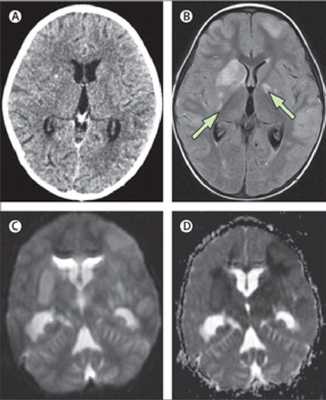

(A) нормальный мозг по данным КТ, 3х-летний ребенок с подтвержденным туберкулезным менингитом. (B)Т2-взвешенные изображения с подавлением сигнала от свободной жидкости, проведено в тот же день, что и КТ, на 5ыйдень выраженных клинических проявлений, показывают несколько инфарктов (стрелки) в области базальных ядер. Диффузно взвешенные МР изображения (С, D) показывают, ограничение диффузии в области базальных ядер.